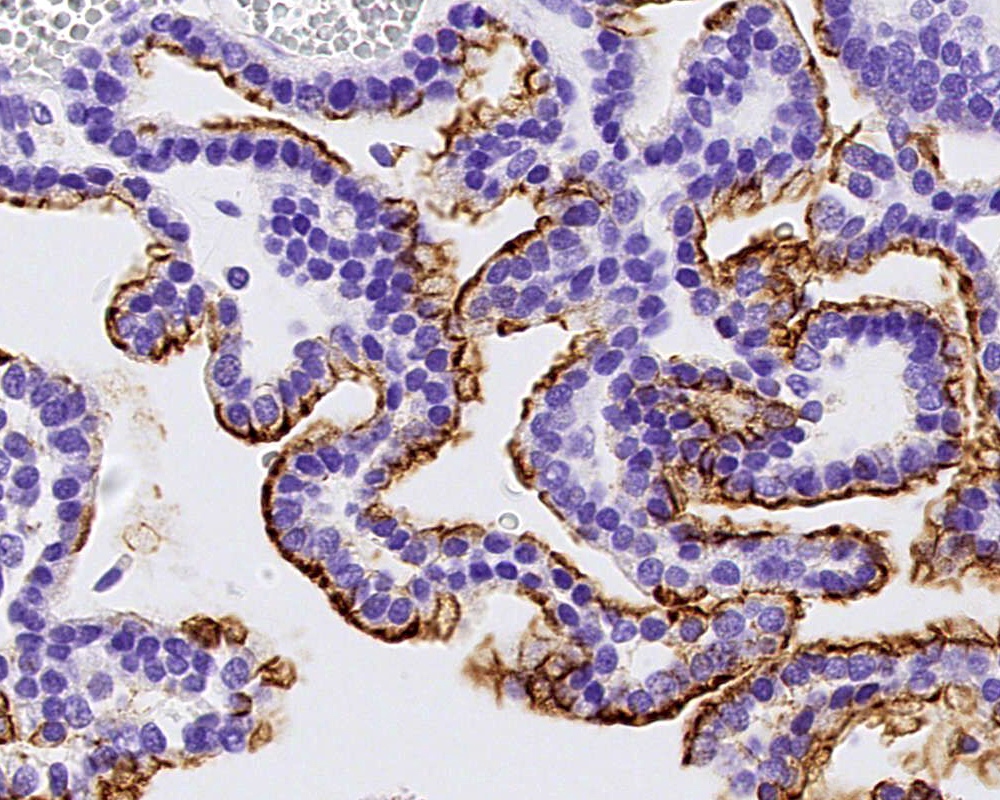

Microscopic (histologic) images

- Choroid plexus papilloma (CPP, WHO grade 1):

- Papillary (finger-like) architecture, resembling normal choroid plexus

- Single layer of cuboidal to columnar monomorphic cells

- Loss of cobblestone surface

- Mild nuclear pleomorphism, mitotic activity rare (< 2/10 high power fields), lacks necrosis

Positive stains

- Transthyretin, KIR7.1, EAAT1, S100, pancytokeratin (cytokeratin, MNF116, AE1 / AE3), CK7 > CK20

- Can be positive for GFAP, synaptophysin, S100